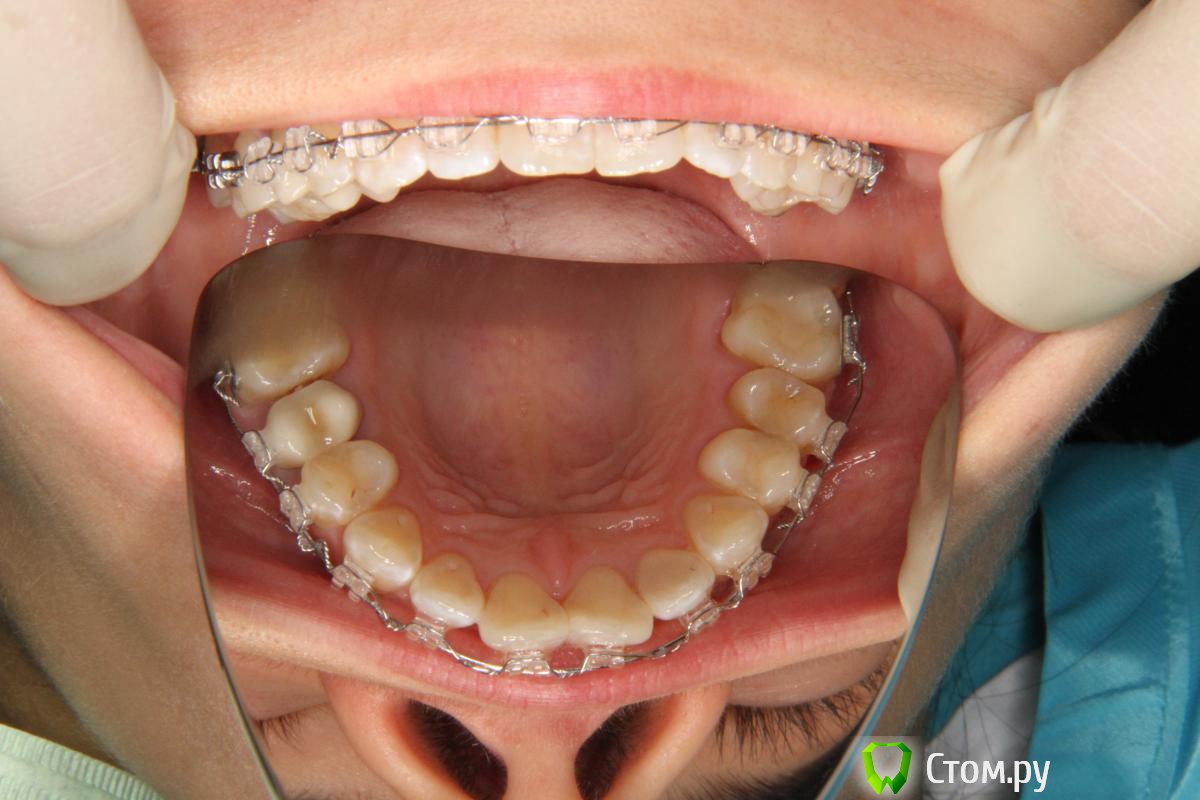

Monkey Опубликовано 20 мая, 2014 Поделиться Опубликовано 20 мая, 2014 Пациентка находится на лечении, основная жалоба - "криво стоят 11 и 21". сейчас получила щель между 16 и 15(дуга сталь 016). Доктора, если дать 8-образную 6-6, уйдет скученность 11-21 (за счет этой щели)? Ссылка на комментарий

m.d.n Опубликовано 21 мая, 2014 Поделиться Опубликовано 21 мая, 2014 Пациентка находится на лечении, основная жалоба - "криво стоят 11 и 21". сейчас получила щель между 16 и 15(дуга сталь 016). Доктора, если дать 8-образную 6-6, уйдет скученность 11-21 (за счет этой щели)? аа зачем сталь поставили ? помоему есть вопрос к ангуляции брекетов на центральных резцах.лечить надо было на 2 челюстях. если увяжите 8кой - скученность станет больше Ссылка на комментарий

Monkey Опубликовано 23 мая, 2014 Автор Поделиться Опубликовано 23 мая, 2014 а зачем сталь поставили ? помоему есть вопрос к ангуляции брекетов на центральных резцах.лечить надо было на 2 челюстях. если увяжите 8кой - скученность станет больше Это начало лечения, низ еще не фиксирован. Потому что сталь жестче.С самого начала давала 8-образную связку 3-3 т.к. у пациентки и так увеличена инклинация резцов (протрузию нельзя допускать) поэтому и встал вопрос - как расправить скученность 11-21? Касательно ангуляции 11,21 - брекеты не могут ее отработать т.к. нет места в зубном ряду для разворота. Ссылка на комментарий

m.d.n Опубликовано 23 мая, 2014 Поделиться Опубликовано 23 мая, 2014 (изменено) Это начало лечения, низ еще не фиксирован. Потому что сталь жестче.С самого начала давала 8-образную связку 3-3 т.к. у пациентки и так увеличена инклинация резцов (протрузию нельзя допускать) поэтому и встал вопрос - как расправить скученность 11-21? Касательно ангуляции 11,21 - брекеты не могут ее отработать т.к. нет места в зубном ряду для разворота.Ну и что что сталь жестче ? какую цель вы преследовали установив стальную дугу. По этим фото мне сложно судить может я ошибаюсь но мне ненравиться позиция брекетов на 11 21 22. 23.контроль опоры у вас выбран неграмотно в таком случае. нельзя просто увязав 6 зубов 2 из которых клыки контролировать их инклинацию.мой вам совет перепроверьте положение указанных мною брекетов- на всякий случай. подключить 2 моляры. поставьте термоактивные дугу- или кунити дуги круглые 0.18 скажем. лучше от системы damon или просто с широкой формой дуги- добавьте гожгориана и band back.И подключайте нижную челюсть. Перейдете на прямоугольные дуги- вот тогда можно немного посепарировать и точно на все место будет Коллега я нехочу вас критиковать - вы спросили я отвечаю.Будут вопросы пишите в личку. Изменено 23 мая, 2014 пользователем m.d.n 1 Ссылка на комментарий